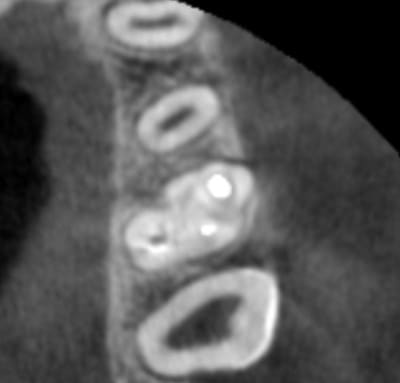

Une jeune fille de 14 m'a été adressée pour retraiter la 26 donc la fistule V ne disparait pas.

Elle n'a pas mal et le sondage ne montre pas de poche >2mm

Sur le CBCT une belle LIPOe avec plus de corticale en V.En DIU d'endo j'ai appris "pas de corticale depuis le collet => avulsion. Puis en bouquinant un peu de cases reports, j'ai tenté des cas similaire et un Retraitement orthograde avec une séance d'hydroxyde ont fait disparaitre la fistule. Les lesions dimunuent petit à petit (j'ai pas assez de recul encore)

il faudrait d'autres images CBCT et ta mire est en

plein sur la zone à étudier;si on regarde la 27

on devine un canal vestibulaire très allongé avec mise en commun mv1 mv2

Suspicion d'un mv2 sur 26;les séances à l'hydroxyde de calcium